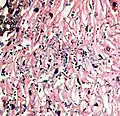

A severe case of candidiasis